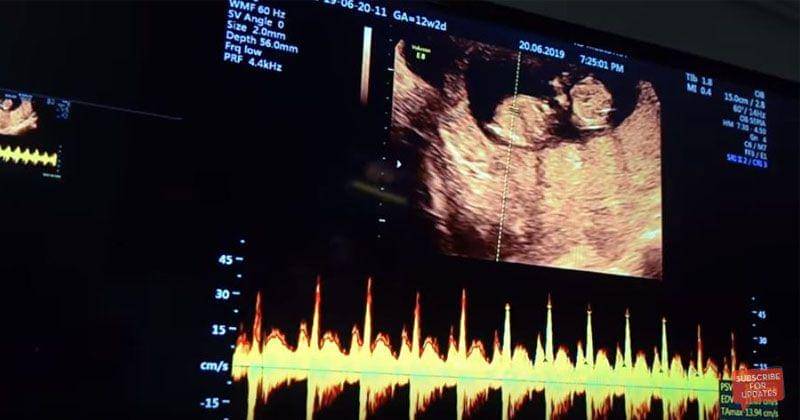

5. Mengecek detak jantung janin

Fakta terakhir adalah proses pengecekan detak jantung janin. Dalam video yang mereka unggah, dapat terdengar dengan jelas suara detak jantung janin yang Irish kandung.

Detak jantung bayi akan mulai berdegup di sekitar minggu ke-enam usia kehamilan, yaitu enam minggu dari hari pertama siklus menstruasi terakhir.

Di masa ini, darah akan mengalir ke dalam embrio dan ada peningkatan detak jantung bayi hingga 100-160 per menitnya.

Dalam video di akun YouTube AishLoveStory sendiri, terdengar suara detak jantung janin yang amat sempurna sebagai pertanda bahwa bayi yang dikandung tersebut berada dalam kondisi yang sehat.